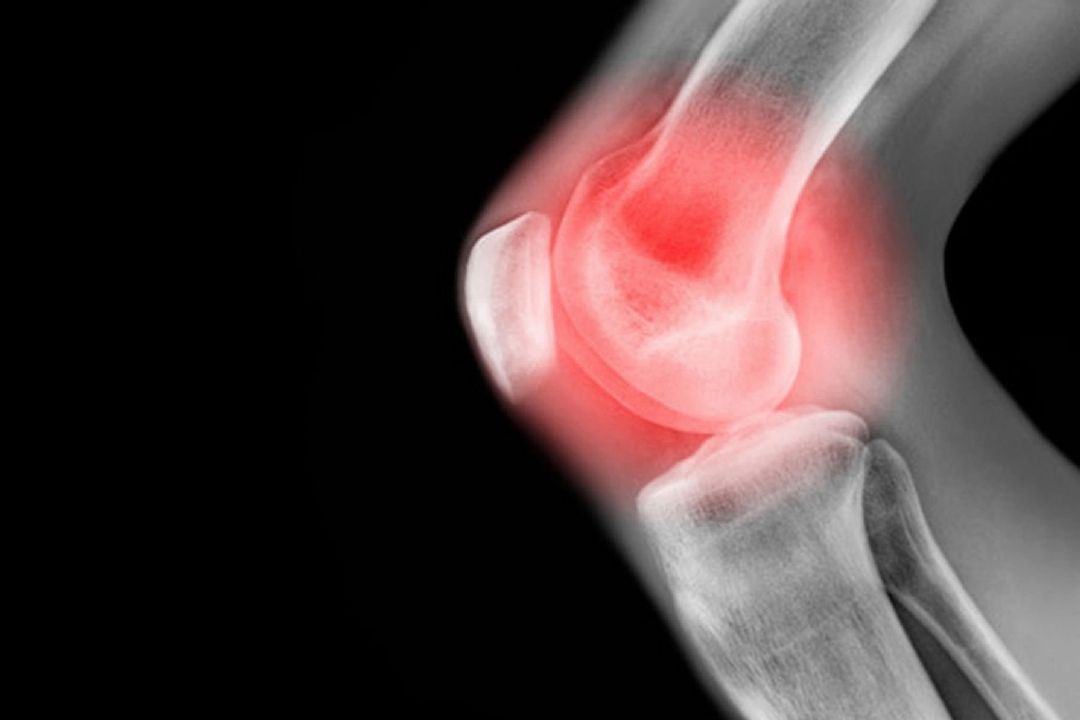

یك متخصص ارتوپدی گفت: آرتروز و ساییدگی مفاصل در نواحی زانو، ستون فقرات و انگشتان دست از شایع‌ترین مشكلات ارتوپدی در سنین بالا هستند و با كاهش فشار و درمان دارویی می‌توان درد ناشی از آن را كنترل كرد.

عضو هیأت علمی دانشگاه علوم پزشكی ایران گفت:درد و تورم، احساس خشكی، محدودیت حركتی و صدای ترق و تروق با حركات زانو؛ از علائم شایع آرتروز زانو است.

آرتروز یعنی چه ؟آرتروز یعنی اسیب دیدن وتخریب سطوح مفصل وازطرفی ضخیم شدن استخوان زیر مفصل وپیرشدن بافت مفصل كه كارایی مفصل ازبین می رود ودرد ایجاد می شود.

تخریب مفصل، غضروف مفصلی است كه در ادامه باعث می شود بافت استخوانی شروع به ساییده شدن كند و مفاصل سفت و دردناك می شود.